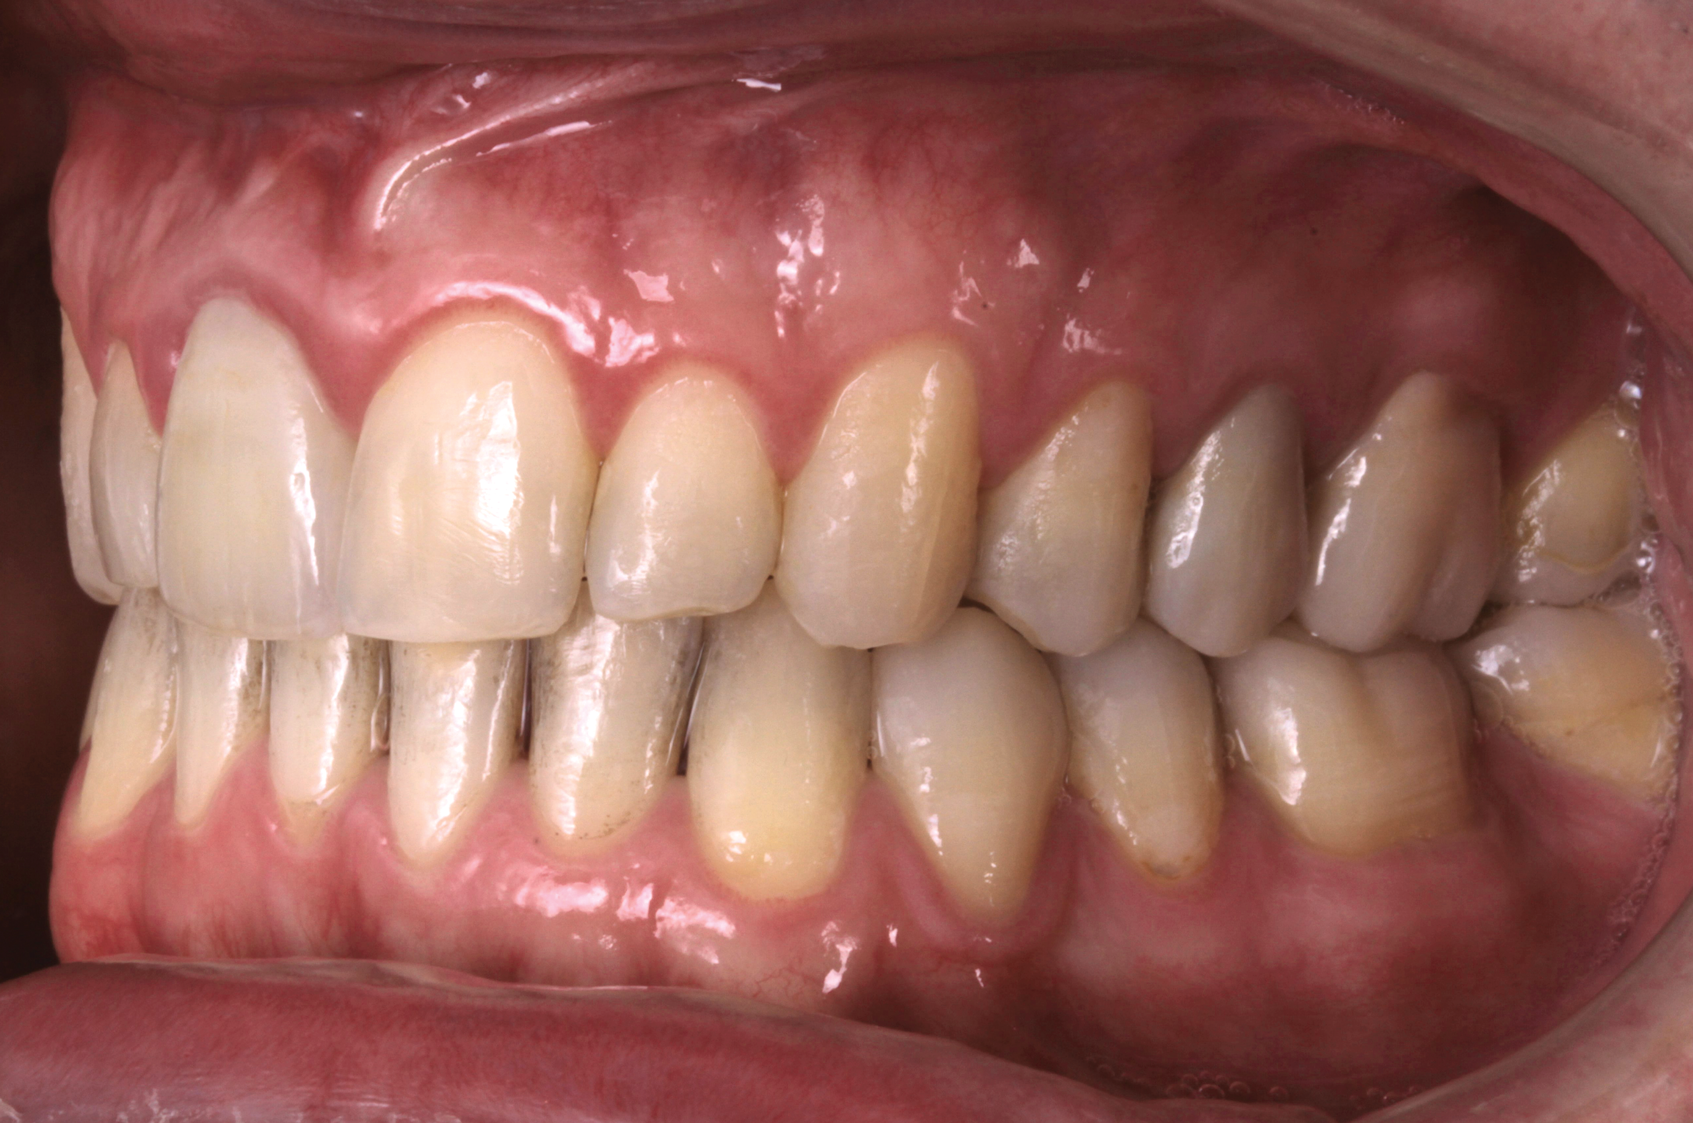

Fig 8. A class III adult male patient required surgical orthodontic treatment. The patient had anterior and posterior crossbites and required leveling of a deep curve of Spee during presurgical orthodontics.

Fig 9. A class III adult male patient required surgical orthodontic treatment. The patient had anterior and posterior crossbites and required leveling of a deep curve of Spee during presurgical orthodontics.

Fig 10. A class III adult male patient required surgical orthodontic treatment. The patient had anterior and posterior crossbites and required leveling of a deep curve of Spee during presurgical orthodontics.